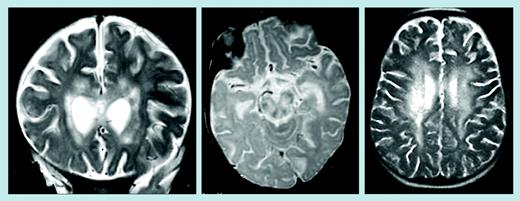

In this issue of Blood, Feldmann and colleagues report on 2 patients affected with FHL presenting initially as an isolated severe and progressive neurologic disorder resembling acute encephalitis and characterized by large lesions of white matter in periventricular areas and brain stem, as seen on magnetic resonance imaging. The clinical phenotype was associated with a missense mutation in the perforin (PRF1) gene, which affected the in vitro cytolytic activity. Based on these data, the authors suggest that PRF1 gene and function should be evaluated in such patients. The results of this study have several implications. First, a rapidly progressive disease involving only one organ, such as the brain or liver, may be per se a sign of an immunodeficiency. It is notable that physicians very rarely suspect an immunologic defect in such cases. Moreover, a few generally accepted diagnostic criteria for FHL are lacking in these 2 patients, thus implying that the current criteria may not be appropriate to identify all patients and thus that an effort should be made to better define clinical and laboratory features.FIG1

Brain magnetic resonance images of patients 1 and 2. See the complete figure in the article beginning on page 2658.